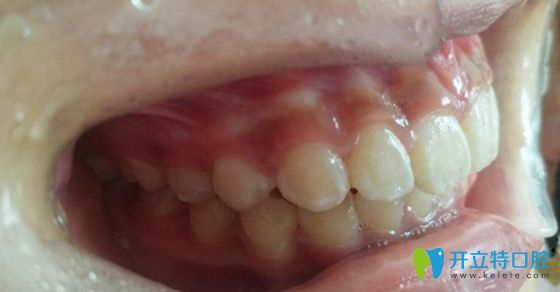

小A在廣州陽(yáng)光樹(shù)口腔做正畸術(shù)前的照片

<深覆合加深覆蓋的牙齒“造型”>

大家誤噴哦,雖然這牙齒確實(shí)有點(diǎn)“一言難盡”........,重點(diǎn)是,影響咬合更影響美觀(guān)。

因?yàn)?,這種類(lèi)型的牙齒通常都伴有上牙唇傾的狀況,而且大多側(cè)面突出(也就是凸嘴),有些還會(huì)出現(xiàn)發(fā)音異常,口呼吸等癥狀。